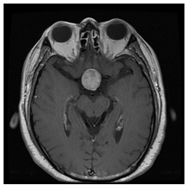

| No Tumor | Glioma Tumor | Meningioma Tumor | Pituitary Tumor | |

| Brain MRI Images |  ![]()  |  ![]()  |  ![]()  |  ![]()  |